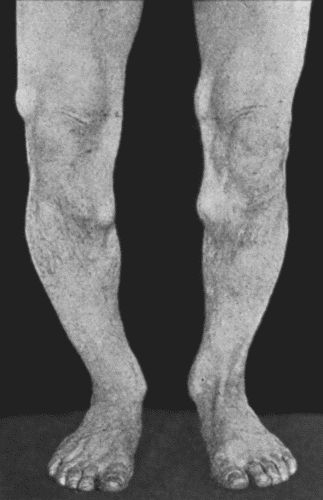

14.Leg Ulcers associated with Varicose Veins 71

19.Tibia and Fibula, showing changes due to Chronic Ulcer of Leg 80